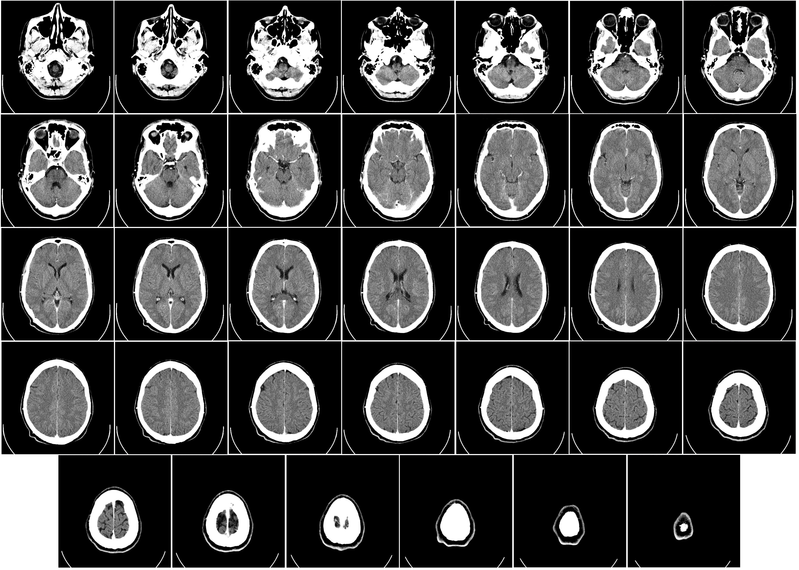

Os animais da linhagem WAR desenvolvem crises epilépticas quando expostos a estímulos sonoros de alta intensidade (120 decibéis) e, por esse motivo, as crises são denominadas “audiogênicas”. “Quando expostos a estímulos agudos, os animais apresentam crises controladas pelo tronco encefálico, chamadas tônico-clônicas e, quando expostos a estímulos crônicos, manifestam as crises límbicas, aquelas mais severas e semelhantes às crises epilépticas do lobo temporal que são vistas em pacientes com a doença”, explicou o biólogo.

Inicialmente, o efeito bloqueador foi observado a partir de análises no comportamento dos animais, sendo confirmada uma atenuação das crises. Outra verificação desse efeito foi por meio de uma técnica laboratorial que detectou em tecidos cerebrais do animal uma proteína específica, a FosB. Essa proteína se acumula e pode ser quantificada em neurônios ativados cronicamente como na situação característica das crises epilépticas.

Outra análise feita durante a pesquisa concentrou-se na avaliação de como as crises crônicas e o tratamento com canabidiol (CBD) podem estar modulando, nos próprios neurônios, a expressão de receptores canabinoides do tipo 1 (CB1). O CBD participa da modulação de diversos processos cerebrais através de muitos mecanismos. Um deles é o do sistema endocanabinoide, composto pelos canabinoides endógenos (produzidos pelo próprio corpo) e seus receptores clássicos: CB1 e CB2.

Segundo Lopes, alguns estudos mostram que, em pacientes com crises crônicas, os receptores CB1 têm sua expressão alterada em algumas áreas do cérebro, como aquelas importantes para a ocorrência das crises límbicas. O resultado observado na pesquisa foi que o tratamento com canabidiol atenuou o aumento da expressão dos receptores CB1 nas crises crônicas.